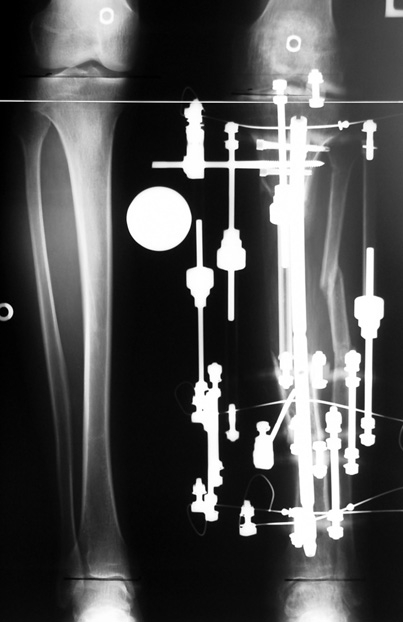

Uygun radikal debridman tüm nekrotik kemik ve yumuşak dokuların çıkartılmasını gerektirir, ve sıklıkla uzuvda instabiliteye neden olur. Kalan kemik ve yumuşak doku defektinin bir şekilde fiksasyonu ve rekonstrüksiyonu gereklidir. İlizarov’un ortaya koyduğu distraksiyon osteogenezi yöntemi, kaynamanın elde edilmesi, deformitenin düzeltilmesi, bacak boy eşitsizliğinin giderilmesi ve segmental defektlerin rekonstrükte edilmesi için başarıyla kullanılmaktadır.

Eksternal fiksatör ile geçen süre (eksternal fiksasyon indeksi), gereken distraksiyon miktarına bağlıdır ve bu süre boyunca bazı komplikasyonlarla karşılaşılabilir. Distraksiyon dönemi sona erdikten sonra, distraksiyon süresinin iki katını aşan konsolidasyon döneminde hastalar eksternal fiksatörü zorlukla tolere edebilirler. Yeterli konsolidasyon sağlanmadan eksternal fiksatör çıkartılırsa ise kırıklar, deformite ve kısalık oluşabilir. Hastanın fiksatör ile birlikte geçirdiği sürenin azaltılması ve böylece hasta konforunun ve aktivite düzeyinin arttırılması için intramedüller çivi üzerinden uzatma yöntemi uygulanmaktadır. Bu yöntemde distraksiyon dönemi sona erdiğinde kemiğin içindeki çivi statik olarak kilitlenmekte ve eksternal fiksatör çıkartılmaktadır. Stabilizasyon intramedüller çivi tarafından sağlandıktan sonra konsolidasyon dönemi gerçekleşmektedir. Bu şekilde hem eksternal fiksatörün uzun süre kalmasından hem de erken çıkartılmasından kaynaklanan komplikasyonların önüne geçilmektedir.